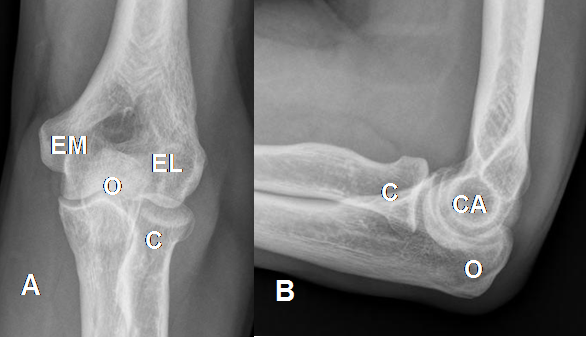

Estructuras óseas a tener en cuenta en el humero distal el capitel, los epicóndilos medial y lateral. Además el olécranon en el cúbito y la cabeza del radio. (Fig 5).

Fig 5. Rx simple de codo. A: AP y B: Perfil.

O: Olécranon. C: Cabeza del radio. EM: Epicóndilo medial. EL: Epicóndilo lateral. CA: Capitel.